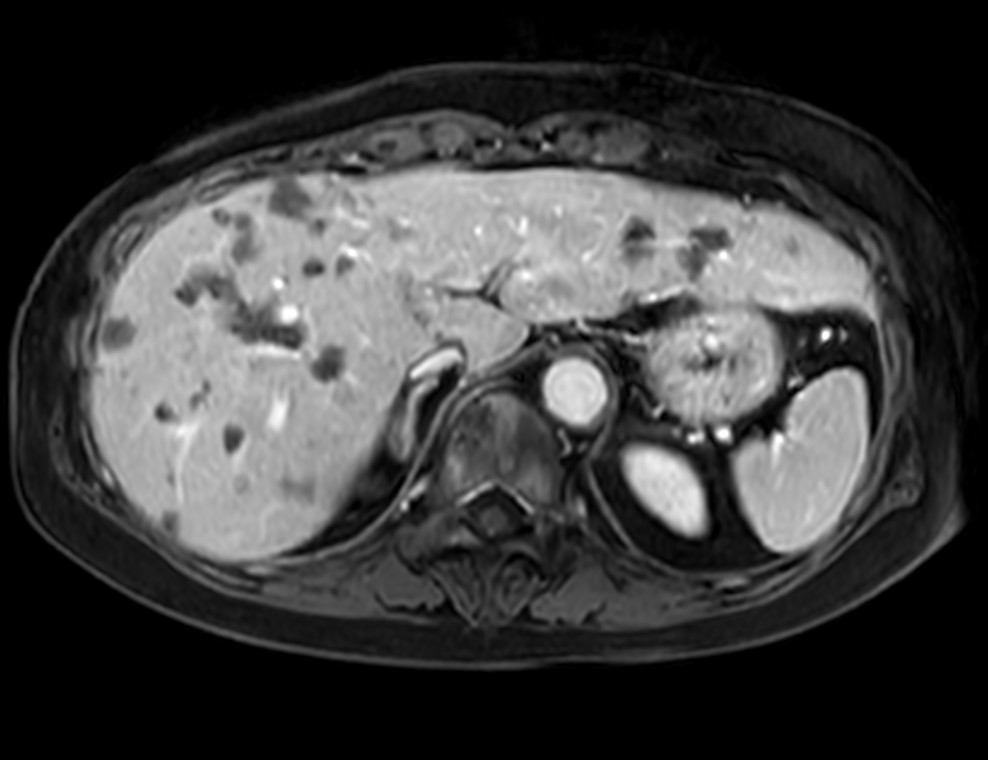

Axial eTHRIVE 2 min Post gado